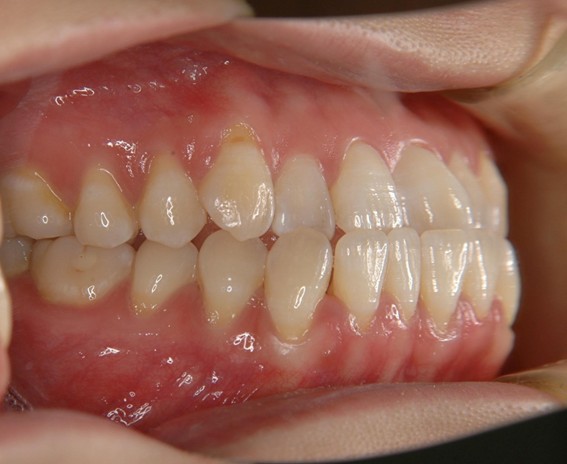

| 主訴 | 前歯が逆に噛んでいるところがある。歯のがたつき。 |

| 治療内容 | 表側ワイヤー矯正、4本抜歯を行いました。 |

| 治療費 | 880,000円+ダイレクトボンディング33,000円(税込) |

| 治療期間 | 30ヶ月 |